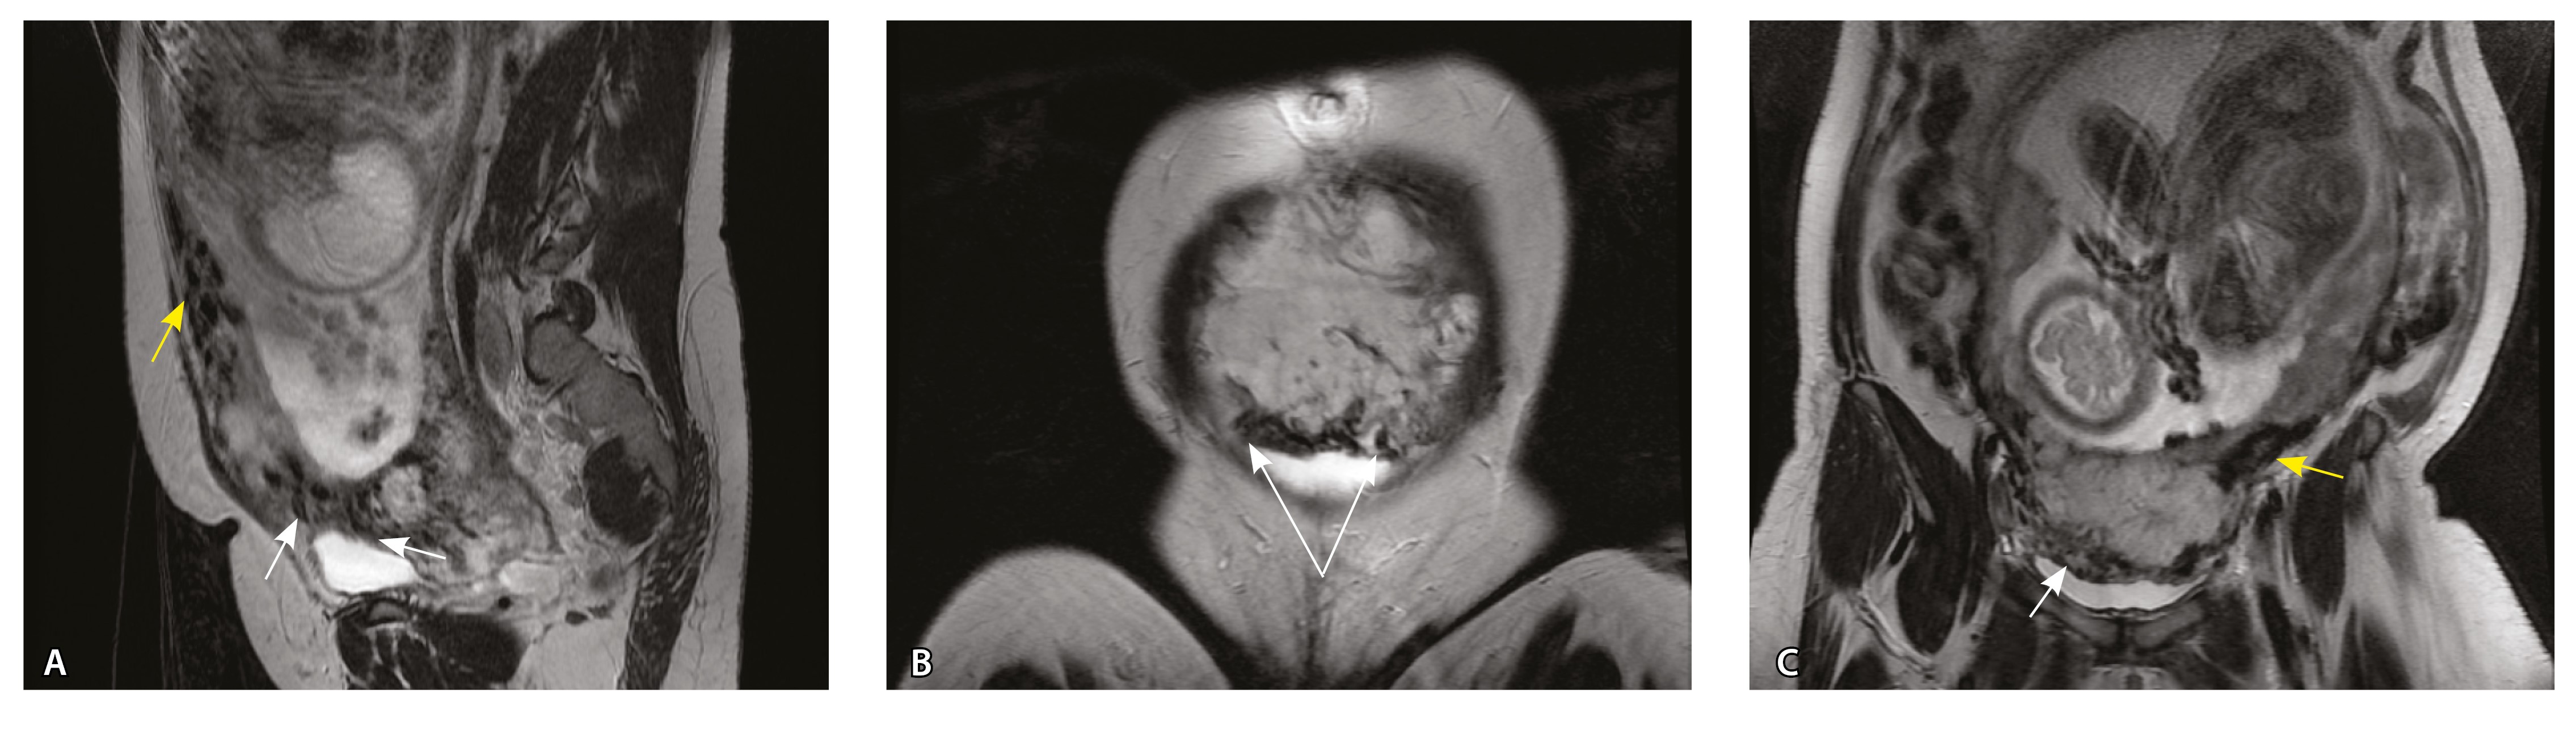

Сосуды 5-го типа. Наличие гиперваскуляризации за пределами матки по данным МРТ, на границе с мочевым пузырем с вовлечением его стенки, сосуды в области перешейка матки, параметрия, в том числе в сочетании с признаками фиброза, наличием рубцово-спаечных изменений и др. Можно предположить, что сосуды 5-го типа являются аналогом pl. рercreta PAS 3b, 3c (рис. 15).

Рис. 15. Беременность 34 недели, pl. percreta, PAS 3b по FIGO (A, Б), PAS 3c по FIGO (В). На магнитно-резонансных томограммах в режиме Т2-взвешенного изображения в сагиттальной (A, В) и аксиальной (Б) плоскостях определяется гиперваскуляризация в области выраженно истонченного нижнего маточного сегмента с распространением сосудов на заднюю стенку мочевого пузыря в области дна (белые стрелки), в область перешейка матки (желтые стрелки)

Данный вариант в патоморфологической картине наиболее сложен для оценки ввиду того, что такие структуры, как параметрий, перешеек матки, стенка мочевого пузыря, обычно не предоставляются в виде макропрепаратов, поэтому визуальные методы, в частности МРТ, могут с большей точностью оценить вовлеченность смежных структур. На микропрепаратах данный вариант инвазии плаценты сочетается с рубцово-спаечными изменениями задней стенки мочевого пузыря с нижним маточным сегментом (рис. 16).

Рис. 16. Гистологическое исследование маточно-плацентарного сегмента при pl. percreta, определенной по данным магнитно-резонансной томографии. Окраска пикрофуксином по Маллори (красный цвет – мышечные волокна, голубой – соединительная ткань). Стенка мочевого пузыря плотно сращена с истонченным маточным сегментом, характеризуется наличием кровеносных сосудов (синяя стрелка). Фиброз задней стенки мочевого пузыря, разобщенные мышечные пучки, замурованные в соединительную ткань (поле отмечено пунктиром). Инвазия ворсин плаценты в бухты миометрия (помечена черным треугольником). Слизистая мочевого пузыря показана стрелкой. Ретроплацентарная гематома помечена звездочкой. Коллаж из 12 фото при увеличении × 100

Как видно на рис. 17, сосуды 5-го типа встречались только при глубокой инвазии плаценты по типу pl. percreta (gr 5) (р < 0,001, хи-квадрат Пирсона).

Сосуды 5-го типа определялись только у пациенток с pl. percreta (77,8%) по данным МРТ (PAS 3b, 3c по FIGO). Визуальная картина была обусловлена наличием гиперваскуляризации по поверхности матки в том числе на границе с мочевым пузырем, перешейком матки и параметрием. Нередко подобные изменения сочетались с признаками фиброза. При патоморфологическом исследовании в этой группе пациенток признаком pl. percreta считался рубцово-спаечный процесс с задней стенкой мочевого пузыря, в том числе в сочетании с сосудами 4-го типа, что было обнаружено всего у 2 пациенток. В то же время в литературе рl. percreta описана как редкое проникновение ворсин за пределы серозной оболочки матки в соседние органы (заднюю стенку мочевого пузыря, перешеек матки, параметрий), подтвержденное патоморфологически, хотя представленные случаи достаточно дискутабельны и не имеют четкого патоморфологического подтверждения [21, 22]. В нашем исследовании не удалось обнаружить ворсины хориона за пределами матки в смежных органах ни в одном из наблюдений. По нашему мнению, истонченный нижний маточный сегмент вместе с различного рода гиперваскуляризацией серозной оболочки матки не может быть единственным достоверным признаком pl. percreta, так как в составе стенки определяется атрофичный миометрий с рубцовой тканью и серозная оболочка матки оказывается неповрежденной. При этом такие структуры, как параметрий, перешеек матки, стенка мочевого пузыря, обычно не предоставляются для исследования в виде макропрепаратов, а в процессе операции удаляется лишь часть стенки матки. Ввиду этого сосуды на наружной поверхности матки лучше визуализируются при инструментальных методах исследования, а не при гистологическом исследовании. В ходе оперативного лечения сосуды могут быть повреждены, также они спадаются, меняется их кровенаполнение, поэтому картина МРТ может существенно отличаться от патоморфологической. Тем не менее проведенный нами анализ сосудов стенки матки показал четкую корреляцию между увеличением диаметра и количества сосудов как в миометрии, так и в составе серозного покрова матки с увеличением степени приращения плаценты. Ряд патоморфологов по-прежнему считает pl. percreta мифом. Но в клинической практике и в практике врачей-рентгенологов на основании МР-признаков данный вариант приращения выделяется и занимает важное место. Для наиболее точной диагностики данные патоморфологического исследования, визуальных методов диагностики, в частности МРТ, интраоперационная картина должны быть оценены не по отдельности, а в совокупности [23].